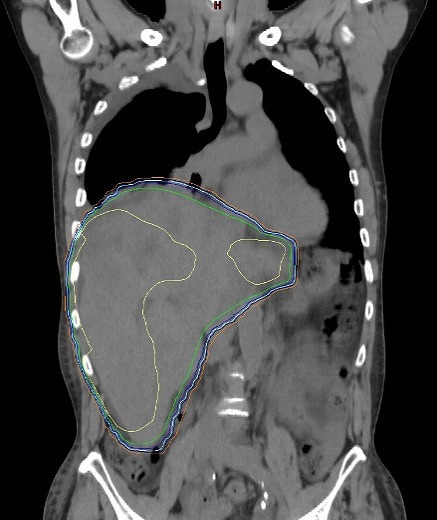

肝内胆管がん。多方向から腫瘍に対してピンポイントで照射(体幹部定位放射線治療)。